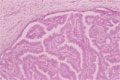

Microscopic image(HE stain, low power view):In mammmary ducts, tumor epithelium forms a projected papillary structure with fibrous core.